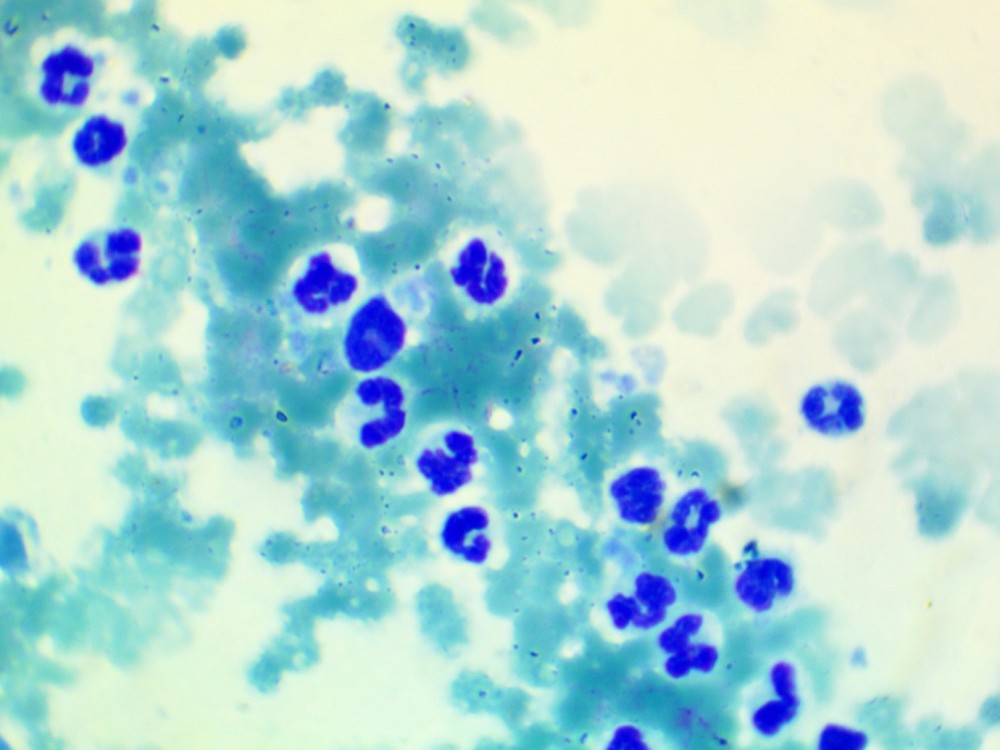

간 병변에 대해 초음파 유도 세침흡인을 시행한 결과, 다수의 호중구 침윤과 퇴행성 변화, 그리고 괴사성 debris가 관찰되어 화농성 염증이 강하게 의심되었습니다.

실제로 세포검사에서는 neutrophilic inflammation이 확인되었으며, 일부 호중구 내에서 세균으로 의심되는 구조가 관찰되어 감염성 병변 가능성이 높았습니다 .

이후 배양검사를 통해 Enterococcus faecalis가 분리되면서, 최종적으로 간 농양으로 진단할 수 있었습니다.